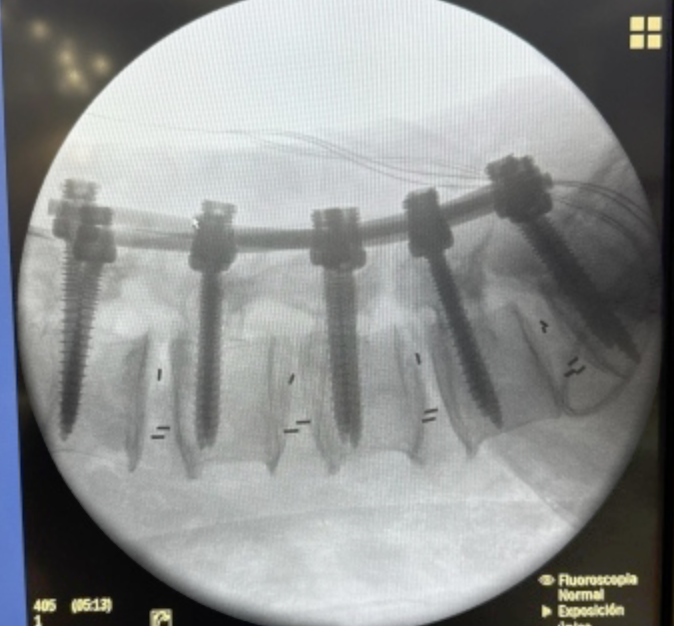

SURGERIES

RESULTS